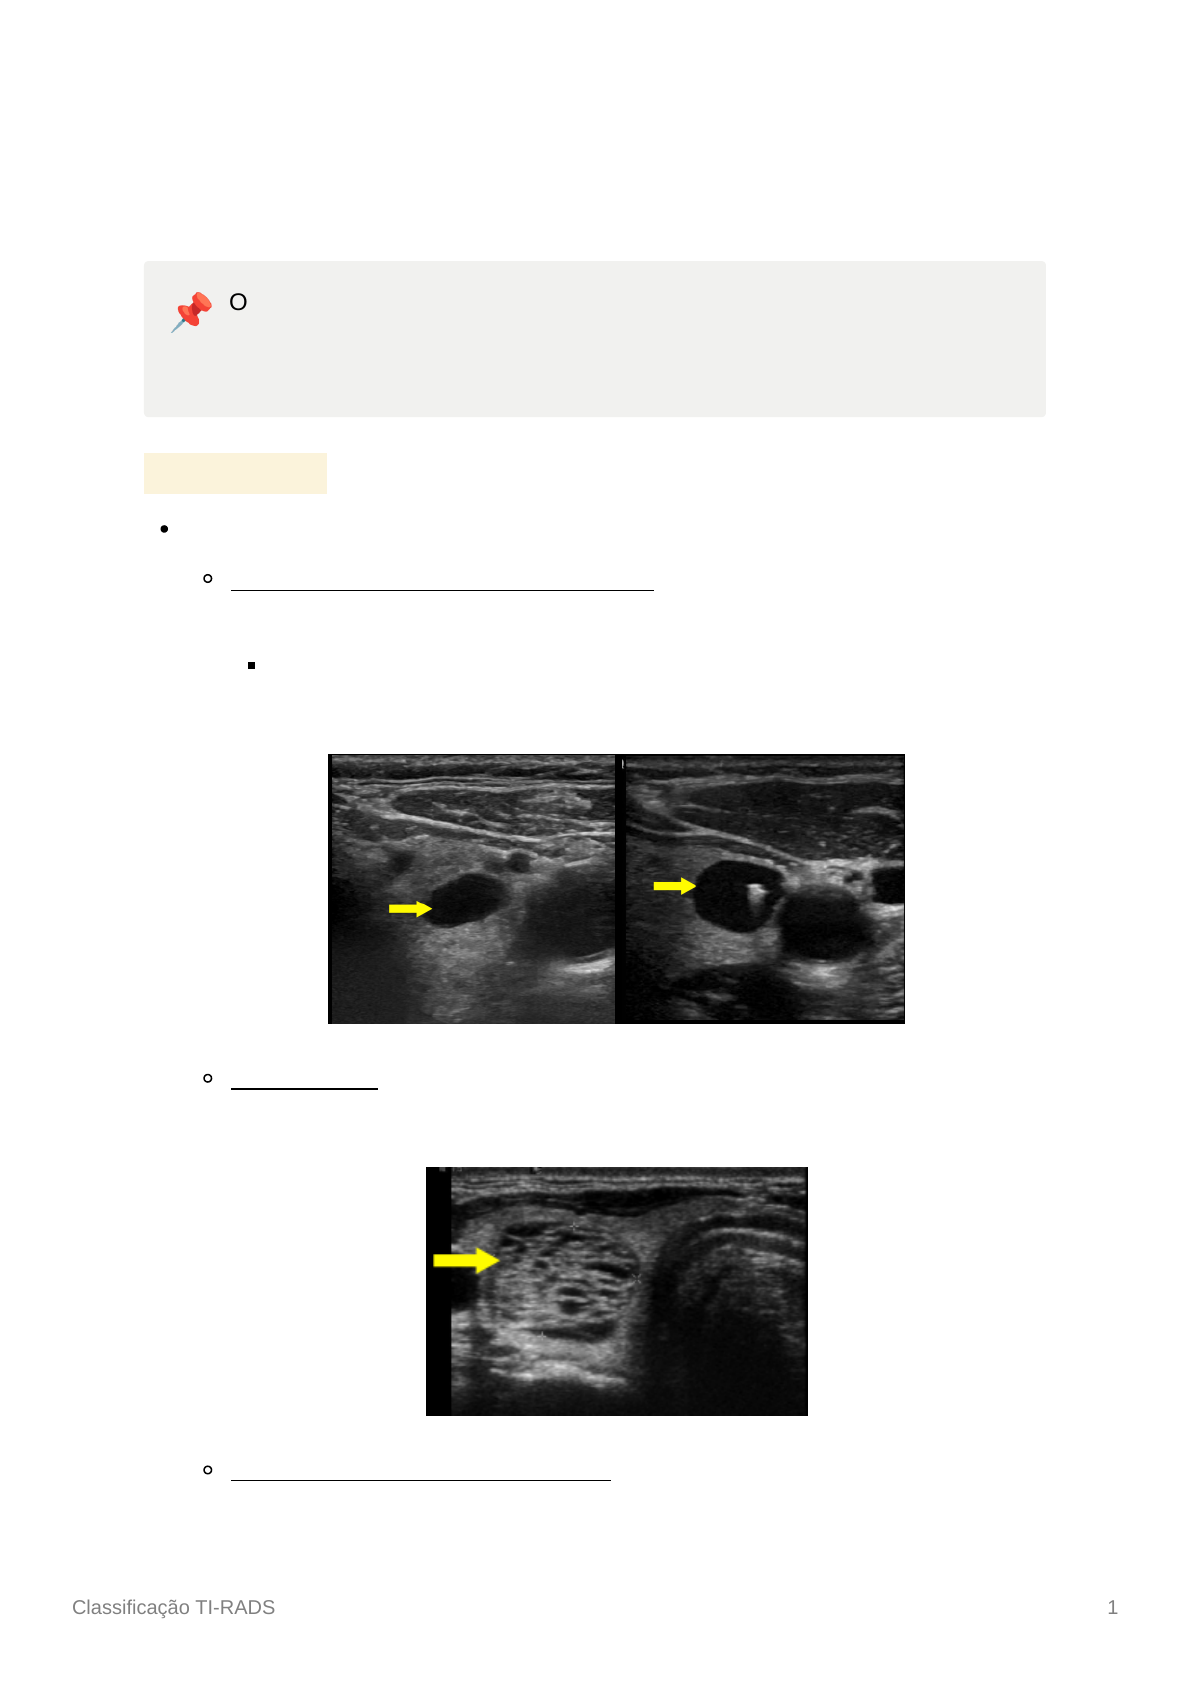

Margens:

Lisas: são bem definidas, sem interrupções

Irregulares ou lobuladas: apresentam interferências no contorno que

formam ângulos agudos. Podem criar protrusões para os tecidos adjacentes

Esse achado é suspeito para malignidade

Extensão extratireoidiana: os limites do nódulo ultrapassam a borda da

tireoide, invadindo outras estruturas

Mal definidas ou indefinidas: dificuldade de distinção entre os limites do

nódulo e o parênquima tireoidiano

Nódulo de margens irregulares

Nódulo com aspecto de margens lobuladas

Nódulo invadindo tecidos moles próximas à tireoide